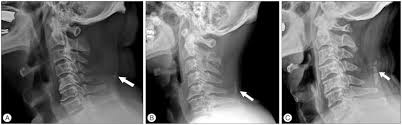

A simple exercise for waking with a stiff neck | ligamentum nuchae. The ligamentum nuchae go from two places on or near the back of your skull and extend through all of the cervical (neck) spinous processes. Ligamentum nuchae — das nackenband (ligamentum nuchae) ist ein paariges band aus elastischem bindegewebe, das als rückenseitige verspannung der halswirbelsäule dient. Ligamentum nuchae — das nackenband (ligamentum nuchae) ist ein paariges band aus elastischem bindegewebe, das als rückenseitige verspannung der halswirbelsäule dient. In chiari malformation treatment, decompression and duraplasty with a harvested ligamentum nuchae showed similar outcomes to pericranial and artificial grafts.3.

Chiari decompression outcomes using ligamentum nuchae harvest and duraplasty in pediatric patients with chiari malformation type i. The ligamentum nuchal is a fibrous membrane, which, in the neck, represents the supraspinal ligaments of the lower vertebræ. The ligamentum nuchae is a large median ligament composed of tendons and fascia located between the posterior muscles of the neck. This ligament connects under the facet joints to create a small curtain over the posterior. Nuchal ligament creates the median fibrous septum in the middle of the muscles of the two parts of posterior neck. ( plural ligamenta nuchae ). Ligamentum nuchae — das nackenband (ligamentum nuchae) ist ein paariges band aus elastischem bindegewebe, das als rückenseitige verspannung der halswirbelsäule dient. It extends from the external occipital protuberance and median.

This ligament connects under the facet joints to create a small curtain over the posterior. In chiari malformation treatment, decompression and duraplasty with a harvested ligamentum nuchae showed similar outcomes to pericranial and artificial grafts.3. The ligamentum flavum forms a cover over the dura mater: A layer of tissue that protects the spinal cord. A medium ligament of the back of the neck that is rudimentary in humans but highly developed and medical definition of ligamentum nuchae. The ligamentum nuchal is a fibrous membrane, which, in the neck, represents the supraspinal ligaments of the lower vertebræ. The ligamentum nuchae is a ligament that forms a strong, fibrous median partition between the muscles of the two sides of the back of the neck. Chiari decompression outcomes using ligamentum nuchae harvest and duraplasty in pediatric patients with chiari malformation type i. Ligamentum nuchae — das nackenband (ligamentum nuchae) ist ein paariges band aus elastischem bindegewebe, das als rückenseitige verspannung der halswirbelsäule dient. Medical definition of ligamentum nuchae: The ligamentum nuchae are very strong. Nuchal ligament creates the median fibrous septum in the middle of the muscles of the two parts of posterior neck. The ligamentum nuchae is a large median ligament composed of tendons and fascia located between the posterior muscles of the neck.